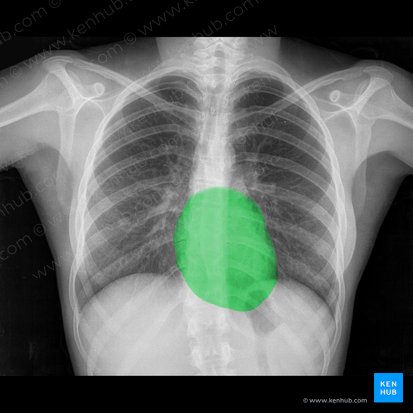

The next feature of the heart that you should evaluate is its size. In a standard PA film, the width of the heart, or rather the width of the “cardiac shadow” (the shadow the heart makes on the film) should appear to be less than 50% the diameter of the chest. If it appears to take up more space than this, the patient may have cardiomegaly due to underlying pathology (or, as previously mentioned, the film could be AP - always check).